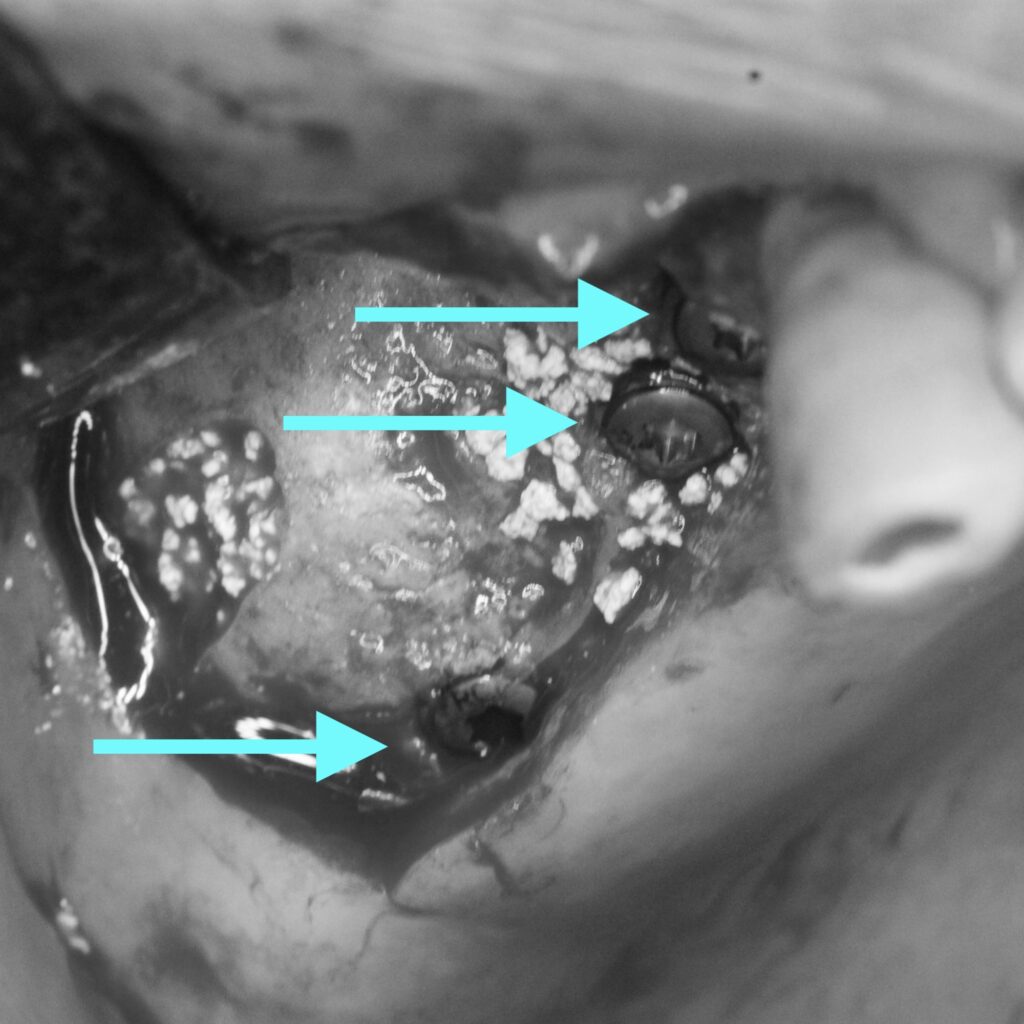

処置後の写真です。

1つ後ろの銀歯も隙間がみられたため、同時に治療を行いました。

歯茎の流れも移行的で、被せ物も綺麗に装着できました。

ブリッジとは違い、1本づつの歯であるため掃除もしやすく歯磨きもしやすい形になっています。